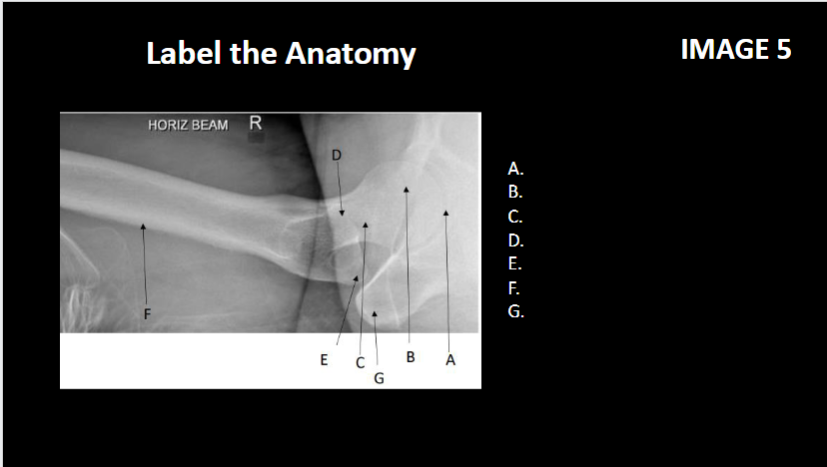

A

Acetabulum

B

Femoral head

C

Intertrochanter crest

D

Femoral neck

E

Greater trochanter

F

Shaft/body of femur

G

Pubic symphysis